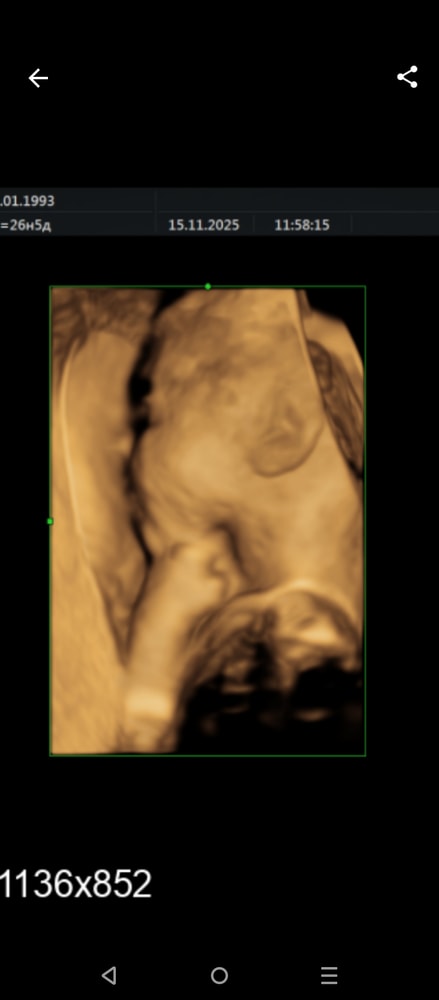

Сходила на УЗИ) 26,5

Целый киллограм человека уже)))

З.Ы. мать с фотками веселится как всегда) веселые УЗИ 😁

Оль, ну класс 😍 Левую часть лица и ушко хорошо разглядели 🥰

Irina Kryl, он в матку лицом воткнулся и не показал личико) ну ухо красивое🤣🤣